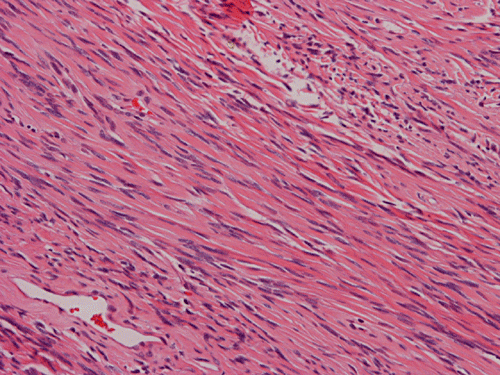

Histologically, the tumor is composed predominantly of strands of collagen fibers arranged in interlacing bundles (Panel F, G, H, I, J ). The histologic pattern is rather homogeneous among different areas and no area with particular hypocellularity or hypercellularity are found (Panel F). In between the collagen fibers are cigar shaped nuclei without high grade features (Panel J). The nuclei and the collagen fibers maintain an interesting regularly randomized relationship reminiscent of a checker board pattern (Panel I). A few small fragments of entrapped, mature bone are also found within the tumor. Mitoses and necrosis are not seen.